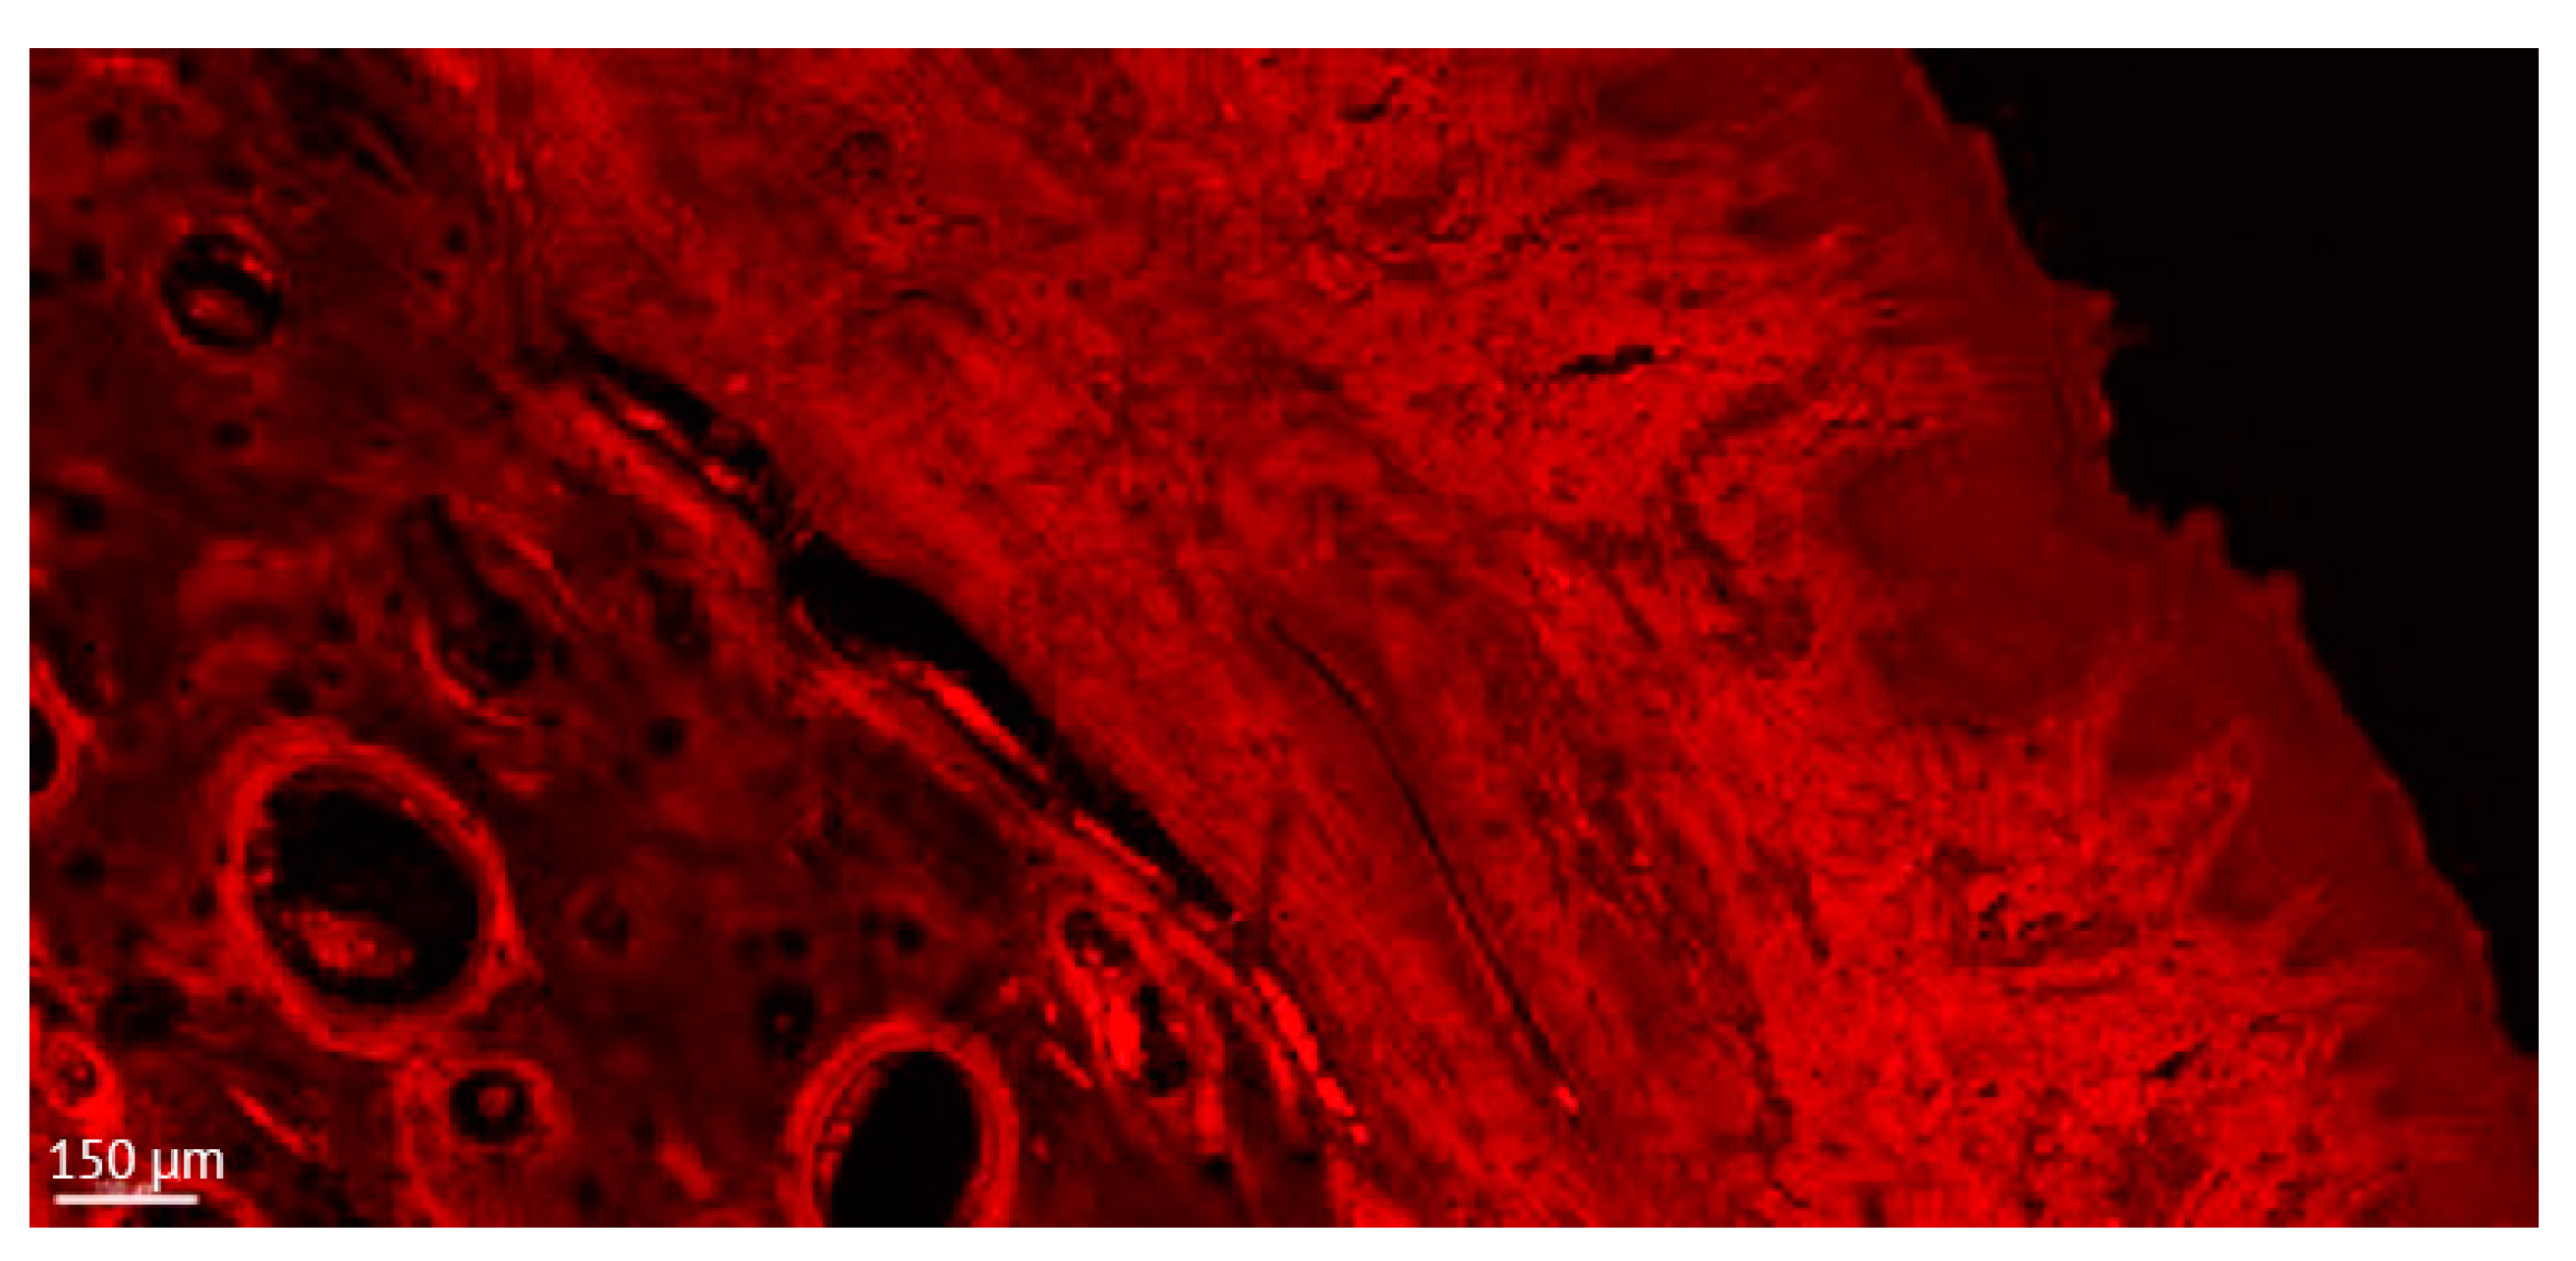

Figure 5.

Detailed aspect of the soft tissue and bone in a thick section of a non-ligated implant. Note the presence of acanthosis of the covering epithelium. ICT is present in contact with bone and implant, promoting an active bone resorption. (implant #2, oral aspect; bar, 150 µm).